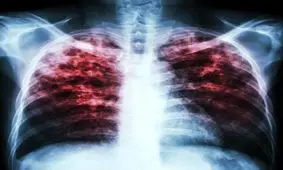

سل یکی از بیماریهای عفونی دیرینه انسان است که با وجود روشهای نوین برای تشخیص و درمان آن، هنوز هم انتشار گستردهای…

سازمان جهانی بهداشت از افزایش موارد ابتلا به بیماری سل در جهان خبر داده است؛ در این مطلب به علائم بیماری سل و…